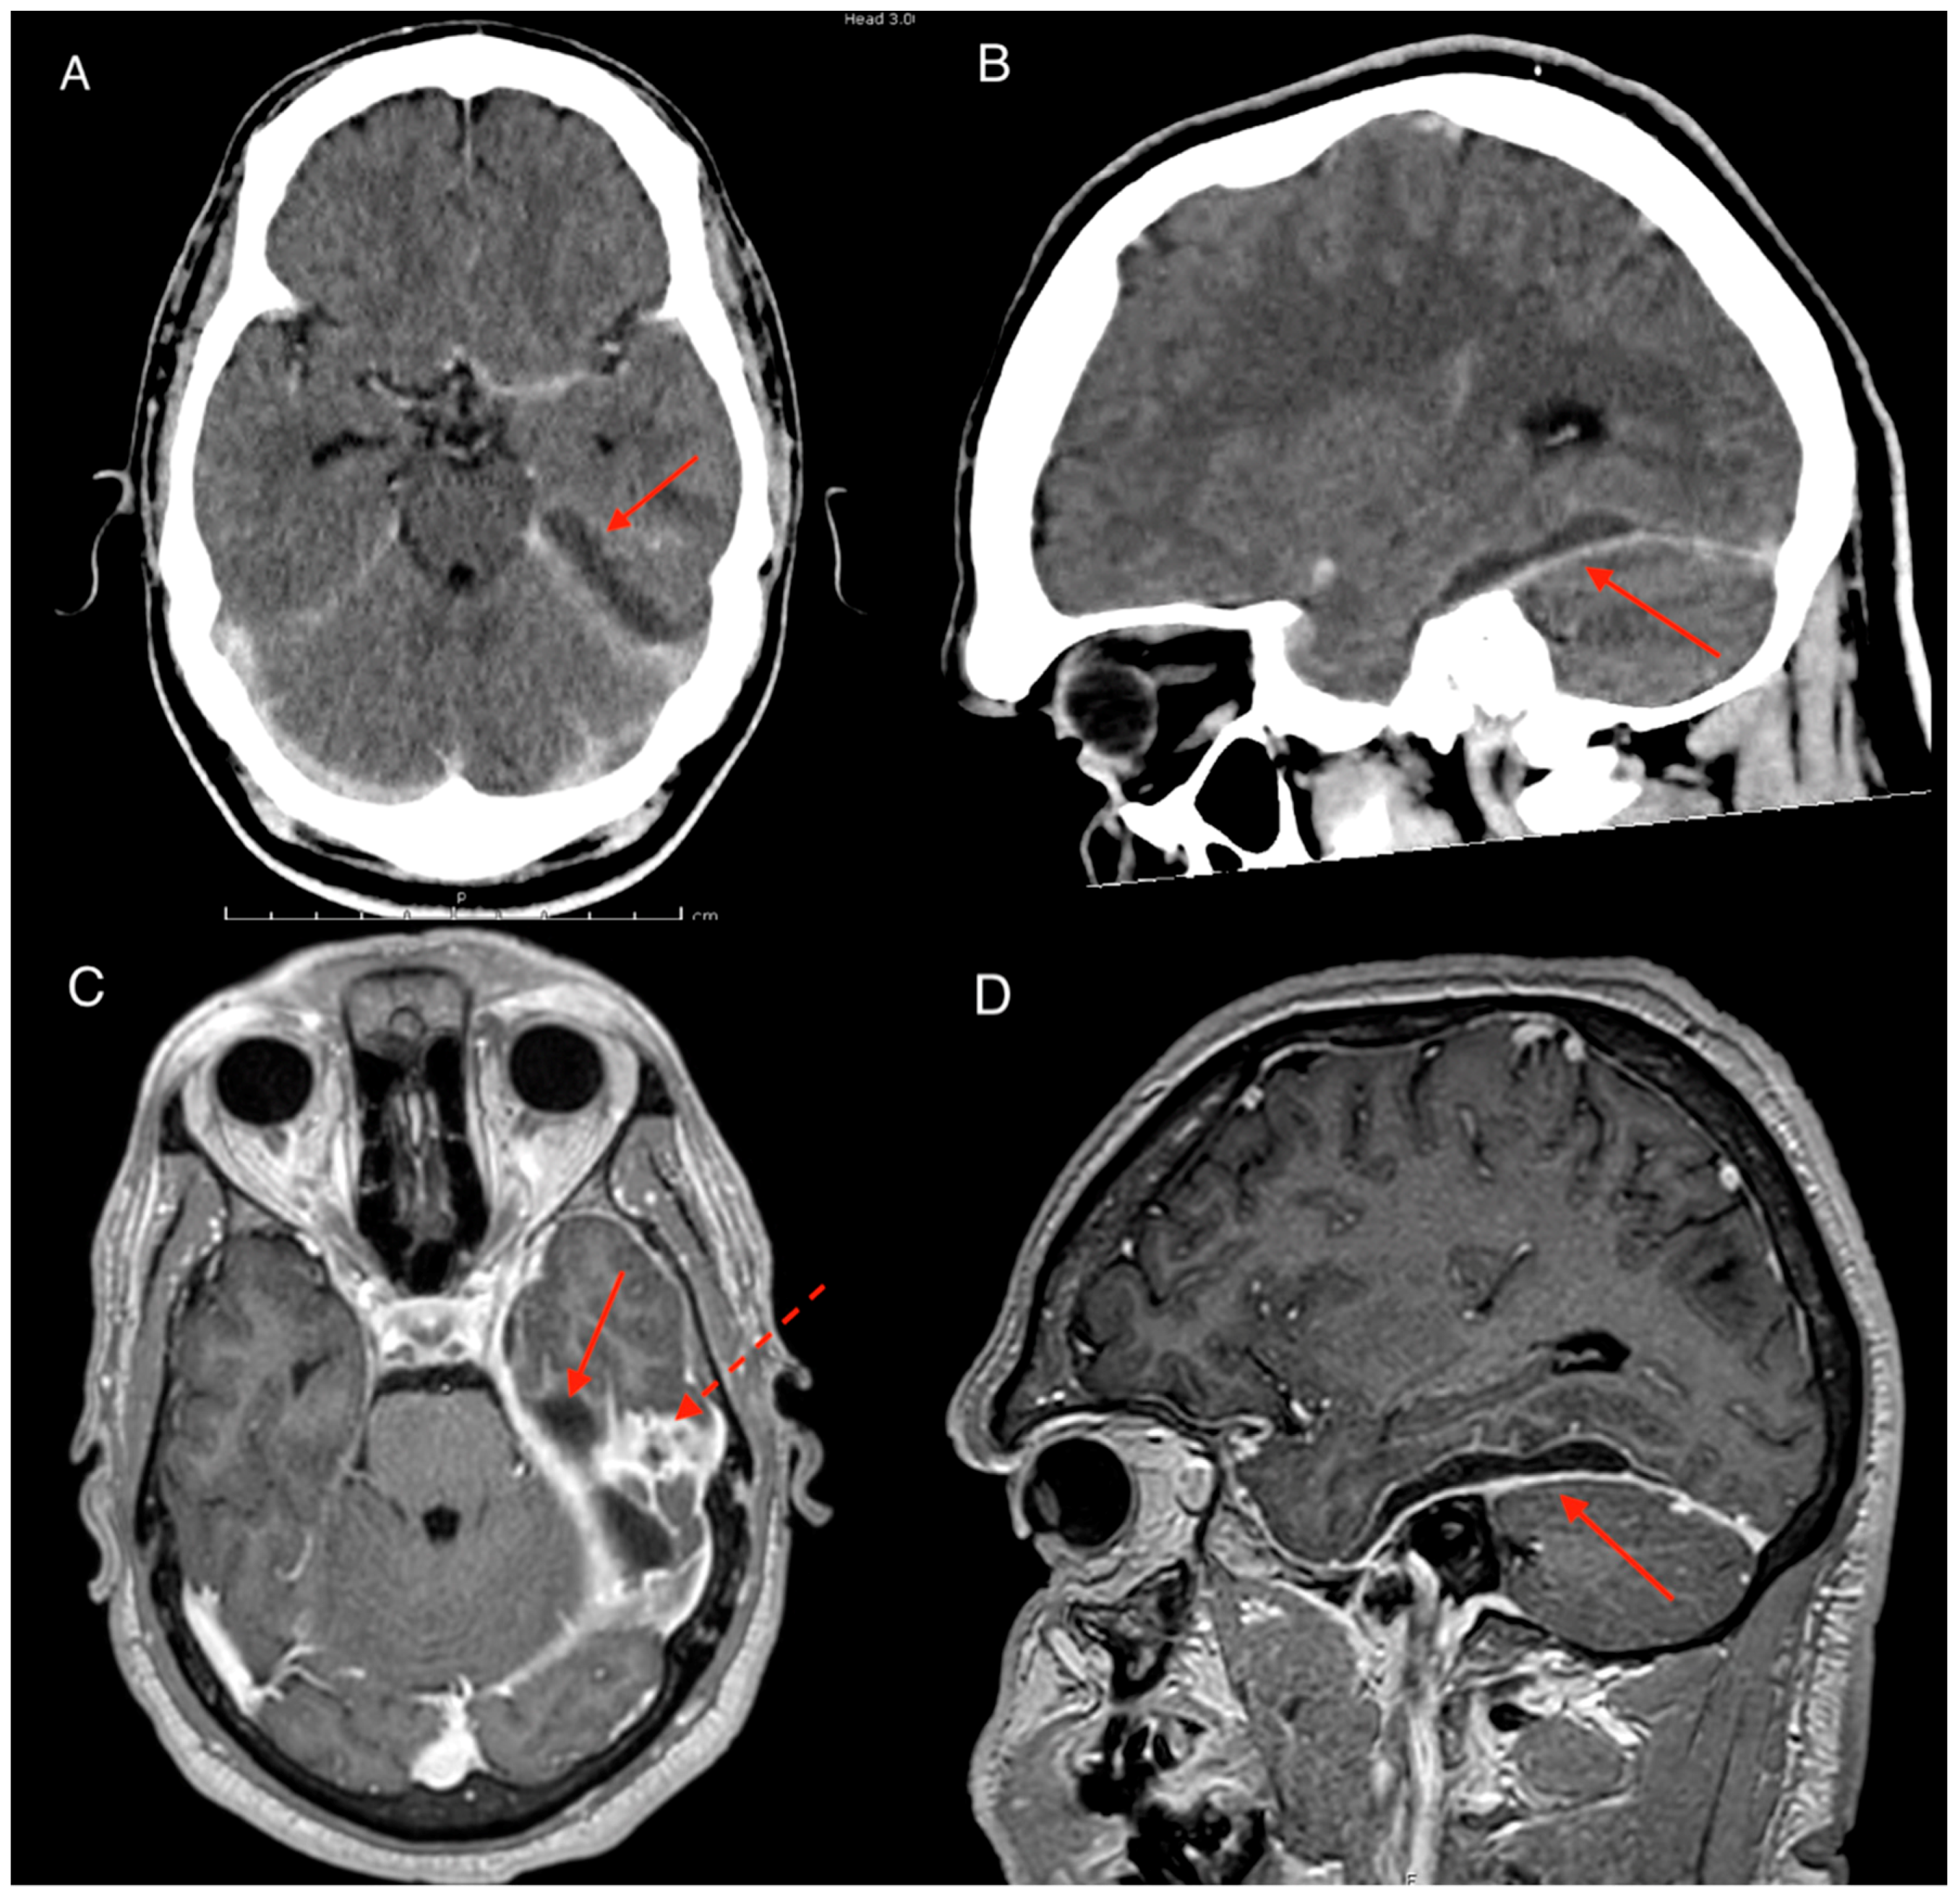

Post operatively, the patient had significant clinical improvement including normalisation of vital signs and blood markers with return to his previous cognitive baseline. A CT scan on post-operative day 1 however revealed a new para-falcine collection located at the left occipital region. Although the patient was well clinically, resolving inflammatory markers plateaued on post-operative day 6 with CRP in the range of 60–100 mg/L and WCC of 14–16 × 109/L. A repeat MRI revealed the para-falcine collection had enlarged with increase in the thickness of the collection wall with new development of intracerebral abscess within the left temporal lobe (Figure 3A–C). After discussion between the infectious disease and neurosurgical team a consensus was reached for occipital craniotomy with re-opening of the previous sub-temporal craniotomy. Intraoperatively, copious amounts of purulent discharge were drained from the new occipital craniotomy, and swabs taken. Dural biopsy was done at the same time which confirmed Scedosporium apiospermum growth which was previously considered possible contaminant. After the second procedure the patient made a marked recovery with both normal vital signs and inflammatory markers of CRP < 5 mg/L and WCC of 7.5 × 109/L within the post-operative week. The ENT team reviewed the patient again under the microscope showing significant improvement of the swelling of the external acoustic meatus. The tympanic membrane was perforated at this time, and free discharge of pus was noted. The decision was made to not perform grommet insertion, in favor of free drainage. Prior to discharge into the community Hospital in the Home program, concerns were raised by clinical staff regarding the possibility of foreign material in patient’s ear. On closer investigation the patient and his father revealed that they had attempted to plug the ear to prevent purulent discharge ruining his clothes and sheets. Education was provided to the family and a loose gauze was applied over the ear for patient comfort. The patient was followed up at 1 month and had no further stigmata of infection with repeat MRI showing no identifiable collection (Figure 3D). Further outpatient reviews at 2 and 3 months revealed no concerns of infection.

Figure 3. MRI brain with contrast. (A & B) Axial and sagittal scans after first surgery illustrating development of intracerebral abscess (red arrow) and development of parafalcine collection (dotted arrow). Note dural thickening and enhancement of the tentorium (yellow arrow). (C & D) Comparison MRI pre-operative to second surgery and then 4 weeks later showing complete resolution of collection in the parafalcine area.